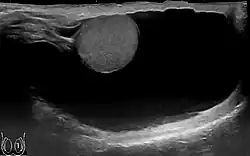

El tipo de hidrocele más común es la hidrocele testis. Es decir, la acumulación excesiva de fluido en el cordón espermático, entre las dos capas de la túnica vaginal que recubre el testículo y la cara interna del escroto.[1] En el hidrocele congénito, el aumento de volumen puede verse acompañado de una hernia inguinal.[2]

En términos coloquiales, el testículo está alojado en una funda o bolsa de piel, llamada escroto. Entre la piel y el testículo hay una pequeña cantidad de líquido, que permite que el testículo sea móvil y lo protege contra posibles traumatismos. El hidrocele testis ocurre cuando la cantidad de líquido aumenta debido a una inflamación de uno o ambos testículos, o por la obstrucción de un vaso sanguíneo o de un vaso linfático. Esto se evidencia con el aumento de tamaño de la bolsa escrotal.[3]

Un hidrocele es un aumento de volumen por causa de líquido en el interior del escroto. Suele asemejarse a un balón suave que por lo general no permite palpar el testículo. Los hidroceles varían bastante en tamaño, generalmente son indoloros y no malignos. Los hidroceles de gran volumen causan considerable incomodidad por razón del tamaño. Como el fluido suele ser transparente, un hidrocele genera luminosidad hacia el lado opuesto cuando se le afronta una fuente de luz, a diferencia de una hernia inguinal. Un hidrocele puede también ser diferenciado del cáncer de testículo, ya que el hidrocele es suave y fluido, en tanto que un cáncer testicular es duro e irregular.